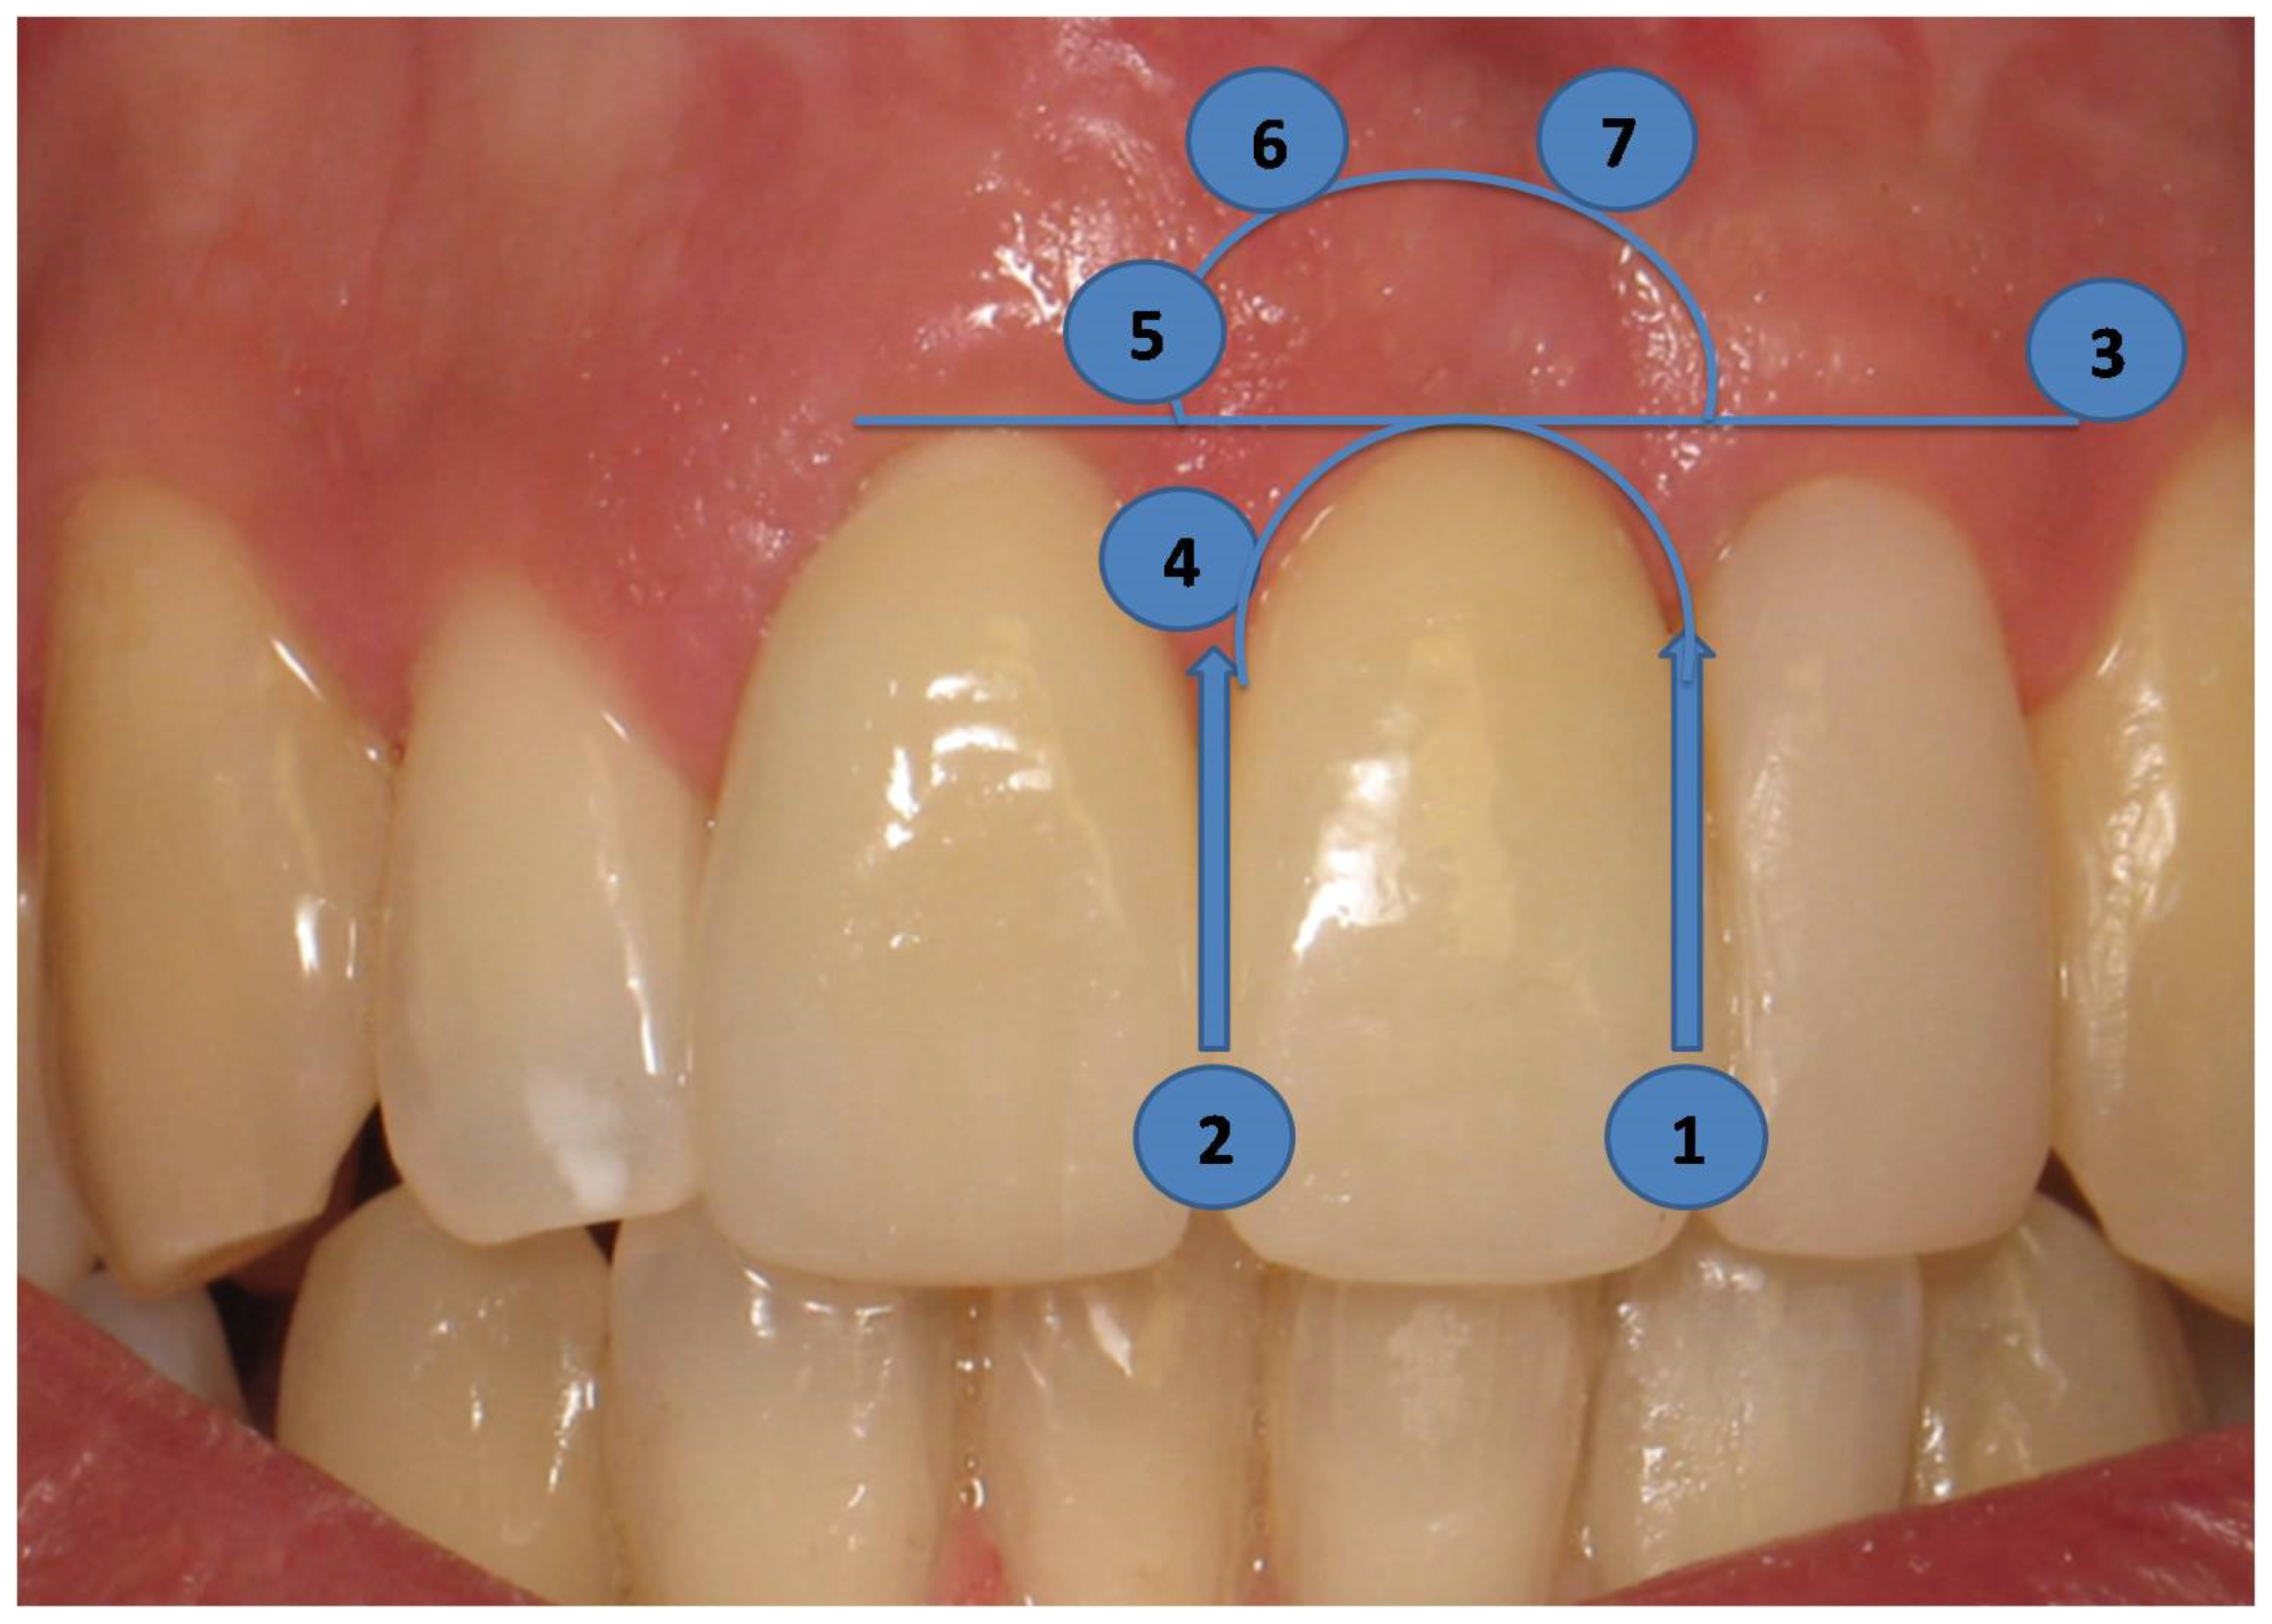

2.4. Long-Term Results of Soft Tissue Esthetic Outcome and Radiographic Evaluation

3.2. PES Assessment